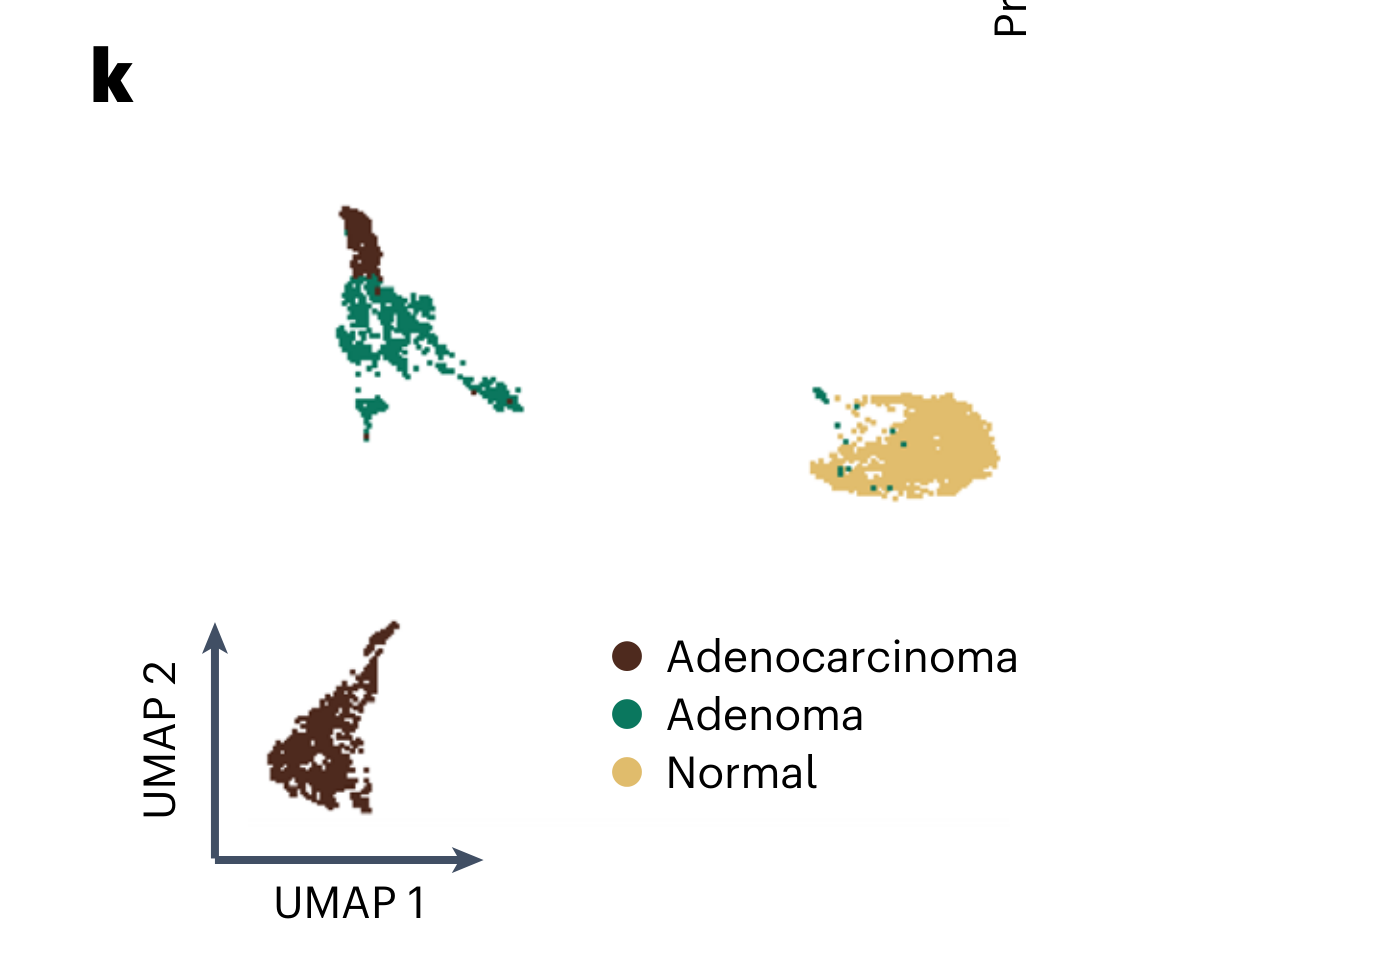

Thuilliez C. et al. - 2024

CellsFromSpace: a fast, accurate, and reference-free tool to deconvolve and annotate spatially distributed omics data

Condition Dimension

N/A

Data Components

Biological AnnotationGene Expression Matrix

Metadata

None

Modality

Imaging-based

Resolution of observation

Cellular

Visualized Elements

Observation

How do IC weight compositions vary across prostate cancer spot clusters in UMAP space?

Chart Type

Dimensionality reduction

Communicative/Contextualization

AnnotationHighlighting

Comparative Design

None

Layout

Spatial : Latent

Scalability Strategy

None (Item-level)